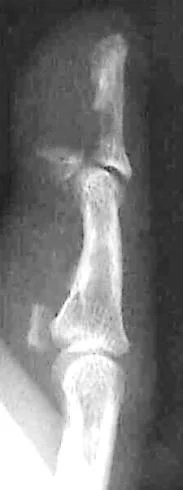

Pathological Fractures

- Fractures caused by trivial force on abnormally weak bone. Seen in:

- Local bone disease

- Osteomyelitis

- Benign tumors and Bone cysts

- Malignant tumors and metastasis

- Generalized disease

- Metabolic: osteoporosis, rickets

- Congenital: osteogenesis imperfecta

- Others: Paget’s disease